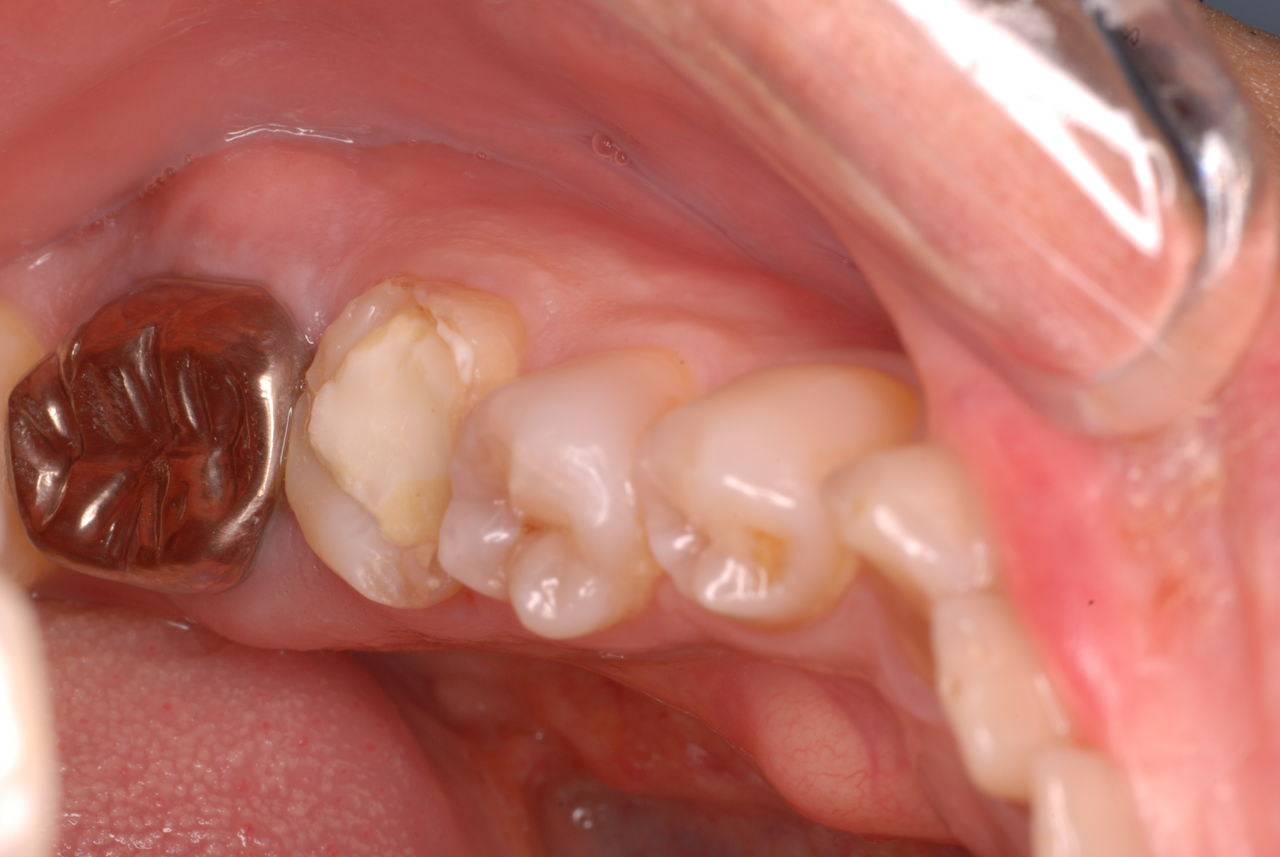

なかなかブラシの使い方ができていないようで、歯磨きと歯周病でのブラシの使い方は別なのですが、習ったことも検査もされずに金属を被せたりしているようで、これからも歯医者さんで抜かれたり、その後にインプラントのような高価な“クギ”を打ち込まれる方が増えるかと思うと残念です。

まず検査をして、ブラシの使い方を習得して歯医者さんで削ったり抜かれたりしないように予防に注意する方々が増えないかと思う日々です。

被せても、詰めても病気は治らないのですから。又病気の元になり易い不適合な差し歯や金属、インプラントがあればそこからバイキンが侵入して体に悪さもしやすいのではないかと心配しています。

全身にバイキンが周り病気の原因になるというのに気づかない方が多いのです。